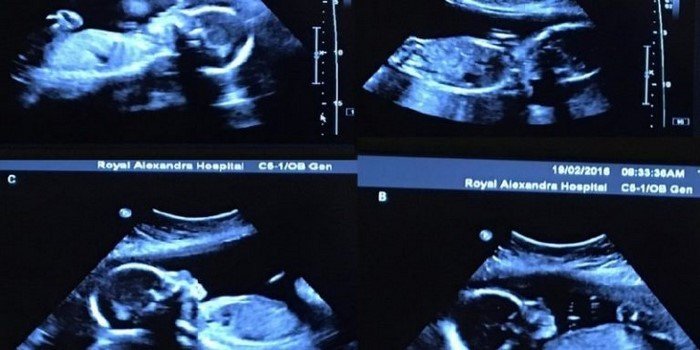

Через несколько месяцев, на плановом осмотре врач вдруг задал Бетани неожиданный вопрос. Медик поинтересовался, были ли раньше в ее роду случаи многоплодных родов. Беременная растерялась, а специалист тем временем вывел на экран изображение.

Обернувшись к монитору, врач принялся считать. «Когда он показал на экране третьего младенца, я подумала — хватит! Но медик не умолкал», — вспоминает сегодня многодетная мать.

Как выяснилось, в животе у Бетани развивалось сразу четыре зародыша. Супруги Вебб признались, что поначалу серьезно запаниковали. А очнувшись от страха, сразу начали прикидывать, как им придется изменить свои планы на будущее.